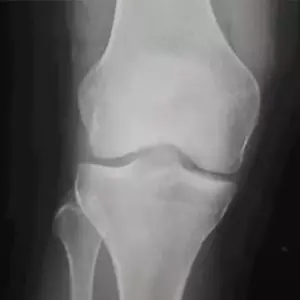

Cirugía de rodilla

Tratamiento a lesiones de rodilla

Evaluación médica y estudios de rodilla

Las rodillas son articulaciones de soporte que, además de proporcionarnos movimiento, nos permiten mantenernos de pie. Son frecuentemente afectadas por traumatismos y/o lesiones (tanto en jóvenes como en adultos) al igual que por desgaste del cartílago. Poseen complicados sistemas de ligamentos, músculos y tendones que hacen posible su labor diaria.

La indicación de una ATR (Artroplastía Total de Rodilla o Prótesis de Rodilla) se fundamenta en el dolor, la impotencia funcional marcada y los signos radiológicos de lesión grave articular en un paciente relativamente sedentario, que no se puedan controlar con tratamientos alternativos (medicamentos orales, inyectados, infiltración dentro de la rodilla de medicamentos, Rehabilitación y terapia física, etc).